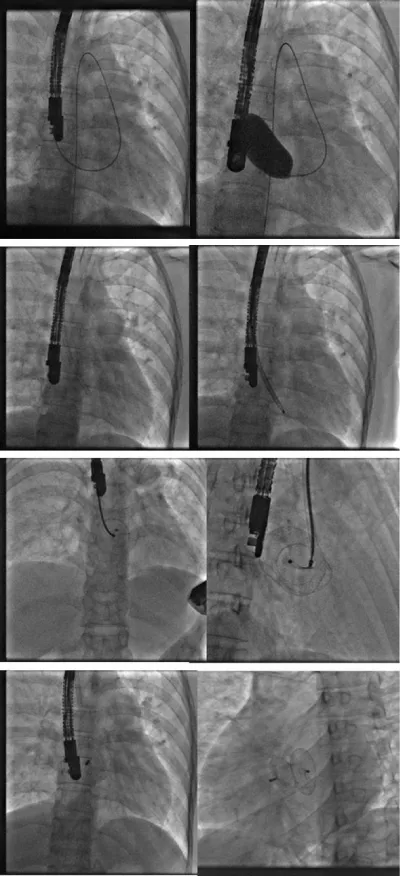

Faced with this trajectory, we suspected an association with an azygos continuation of the inferior vena cava. We interrupted the procedure and requested a CT angiography that confirmed the diagnosis (Figure 2).

Figure 2: Azygos continuation discovered in angiography and CT.